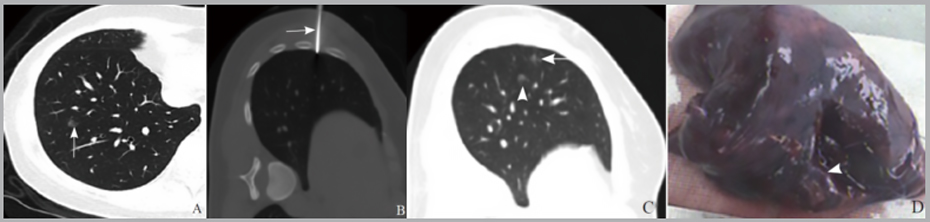

图例:穿刺前后 CT 图像

a:穿刺前;  b: 图2 穿刺中,距离病灶5 mm 处注射医用胶;c: 穿刺后,医用胶注射后形成质地坚硬的胶粒。

VATS术前CT引导下肺结节定位技术

CT引导下医用胶注射在胸腔镜肺部磨玻璃影和小结节手术定位是一种方法可靠、实用性强的病灶定位技术。有助于肺部病灶定位准确、快速、安全、牢固、便捷,提高胸腔镜手术成功率、降低手术难度。

医用胶是指以α-氰基丙烯酸正辛酯、α-氰基丙烯酸正辛酯为主体的一类生物制剂。能够强力黏合机体组织,且速度快,无毒副作用,安全性高。 既不会随着时间的推移而扩散和移位,时间上允许择期手术;术中也可以通过触觉感知到其存在的位置,比较容易的找到病变部位。 此外由于胶水的黏合作用可以封闭穿刺点减少气胸的发生率。

CT引导下医用胶注射能够为胸腔镜下GGO、SPN的位提供准确参考,对于缩短手术时间、控制切除范围、降低手术难度均具有积极意义,且医用胶牢固、便捷的优势,可使得手术时机的选择更为灵活,从而提高手术安全性与有效性,是一种方法可靠,实用性强的病灶定位技术。